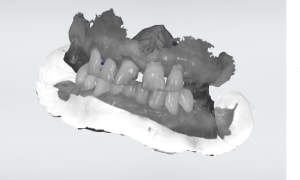

Capture_d_écran_2019-09-04_21.19.10_a55pcs.png